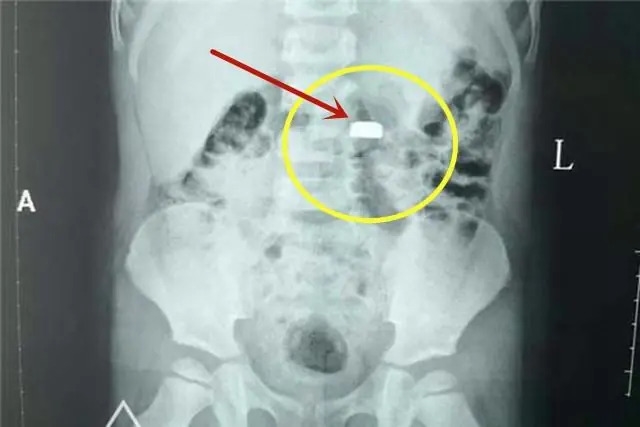

| Viên pin cúc áo mà bé trai 3 tuổi của chị Linlin nuốt phải gây nguy hiểm dù tới bệnh viện ngay sau đó |

Quan trọng nhất, cần nhớ, dù dùng mật ong hay phương pháp sơ cứu nào cũng phải đưa trẻ đi cấp cứu càng sớm càng tốt ngay sau đó. Thông báo rõ hoặc mang theo loại pin trẻ nuốt phải. Bác sĩ sẽ sắp xếp chụp X-quang, CT và ưu tiên phương pháp nội soi để gắp pin ra sớm nhất có thể, ngăn chặn hóa chất rò rỉ phá hủy nội tạng.